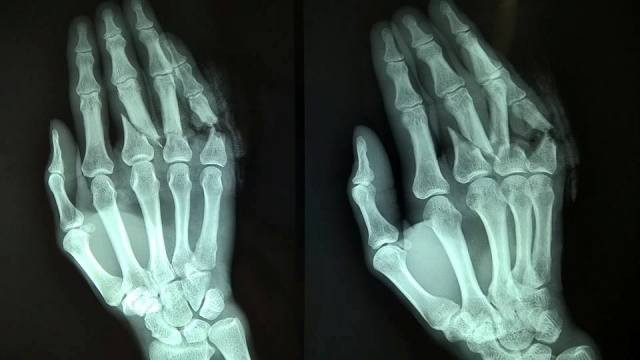

Chụp X-quang để chẩn đoán chấn thương.

Click vào ảnh để xem 4 hình ảnh minh họa